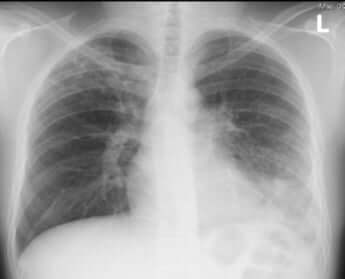

長引く咳の正体は……